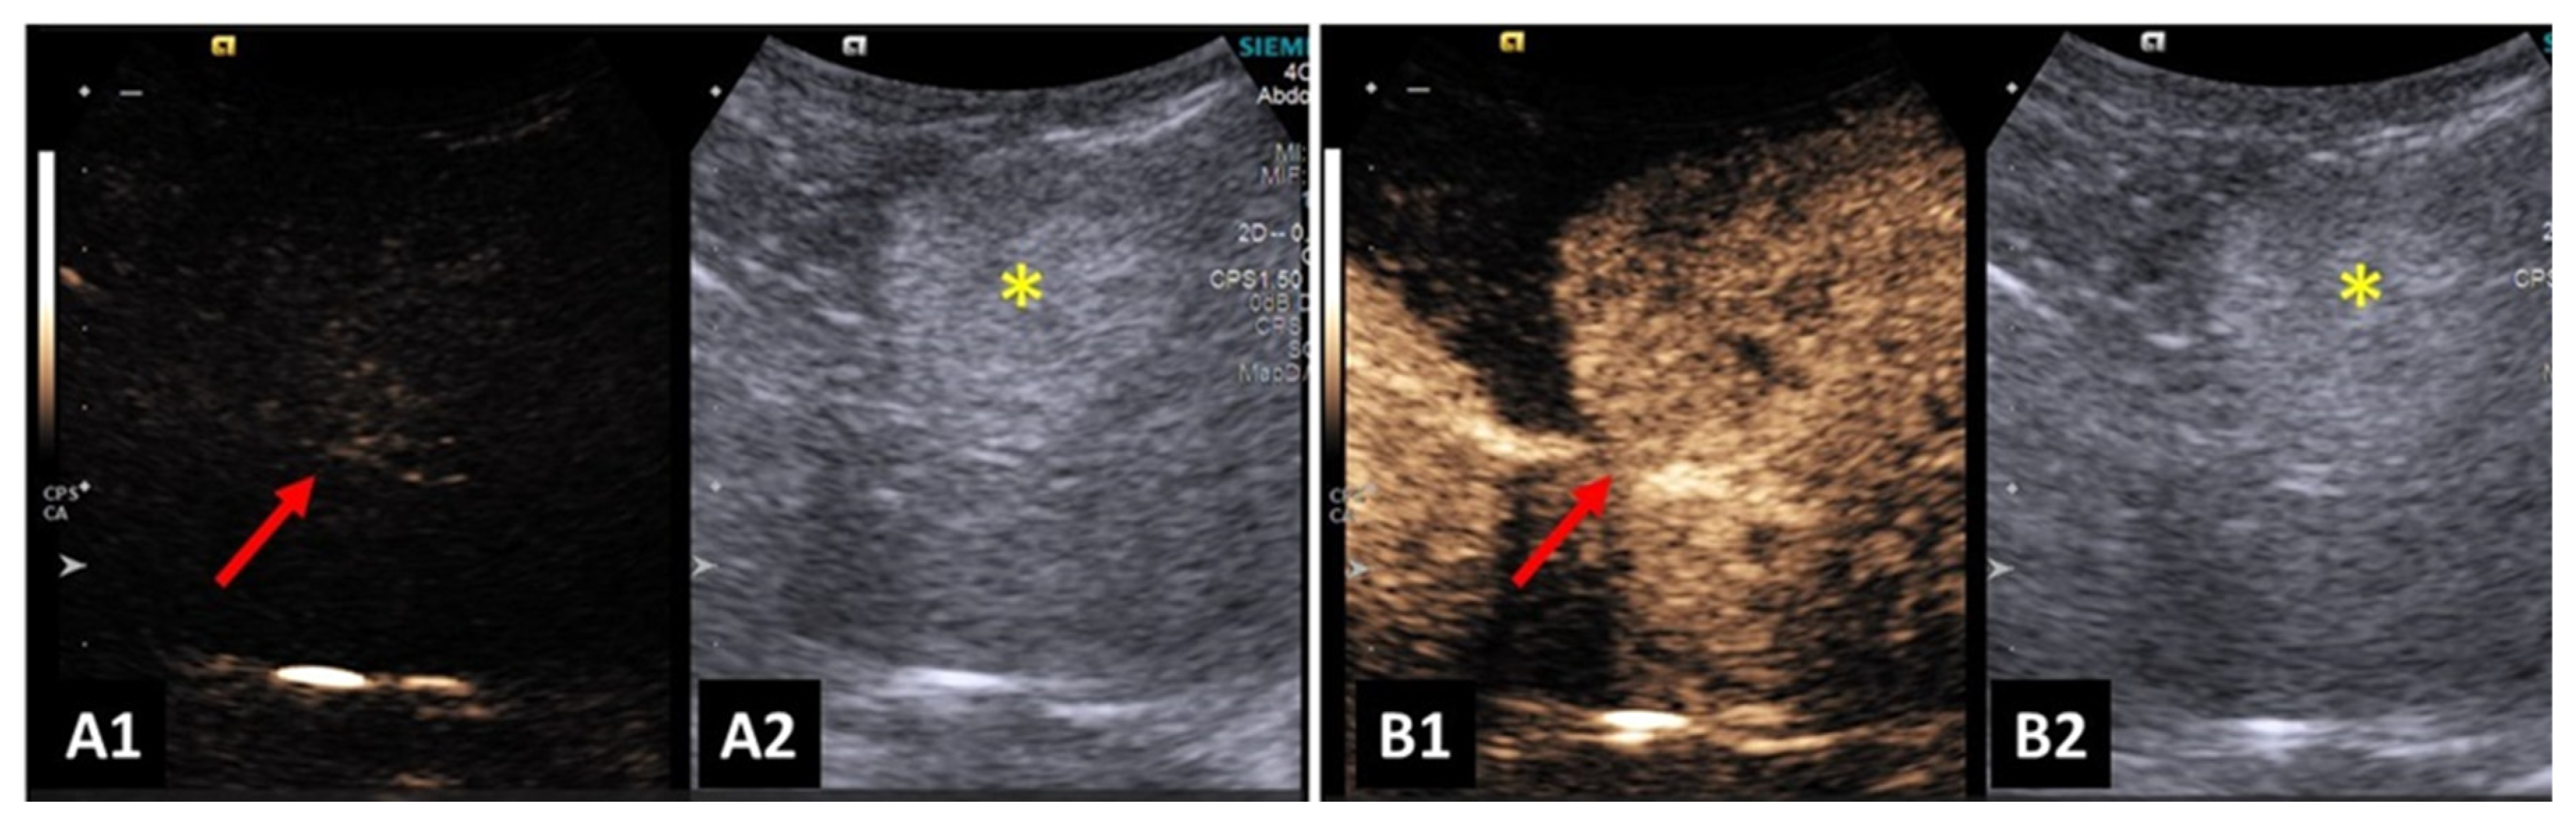

Contrast-enhanced ultrasound enabled an increase in the differentiation of hepatic nodules and normal hepatic parenchyma. There was also higher ability to detect malignant nodules, when compared to B-mode ultrasonography. Benign nodules were less conspicuous and there were no additional nodules detected after contrast-enhancement [57]. An example can be seen in Figure 4.

Hypoechoic nodules detected in the hepatic parenchyma during the peak of contrast were highly suggestive of malignancy [57,58].

Figure 4. Image of a benign liver lesion in a dog: (A1) lesion before contrast filling; (A2 and B2) B-mode image of the hyperechoic liver lesion; and (B1) homogeneous and hyperechoic liver lesion on CEUS.